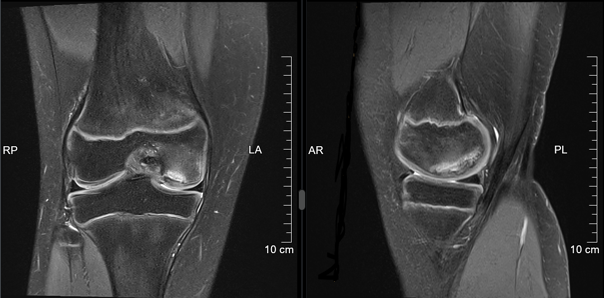

Osteochondritis dissecans

Die Ursache der Osteochondritis dissecans ist multifaktoriell und der Pathomechanismus noch nicht gänzlich geklärt. Das repetitive Trauma spielt eine wesentliche Rolle, häufig sind sportlich aktive Kinder und Jugendliche betroffen. Hormonelle, vaskuläre oder Erbfaktoren können als mögliche Ursache eine Rolle spielen. Die Schmerzen sind belastungsabhängig, im Spätstadium kann es zu Blockaden kommen. Das MRI ist die beste Untersuchung, um das Stadium zu beurteilen und somit das therapeutische Vorgehen zu entscheiden. Meistens handelt es sich zunächst um eine konservative Therapie mit Schonungsmassnahmen und Sportkarenz von 6 Wochen bis 3 Monate. Diese Entscheidungen müssen individuell erfolgen. Zu den operativen Therapien in schweren Stadien gehören die retrograde (knorpelschonende) Anbohrung, arthroskopische- oder offene Refixation. Ist dies nicht möglich, kann bei kleinen freien Gelenkskörpern die Entfernung ausreichen. Bei grösseren Defekten kommen Rekonstruktionen infrage. Grundsätzlich gilt, dass die Prognose bei jüngeren Patienten mit offenen Wachstumsfugen besser ist als nach Fugenschluss.